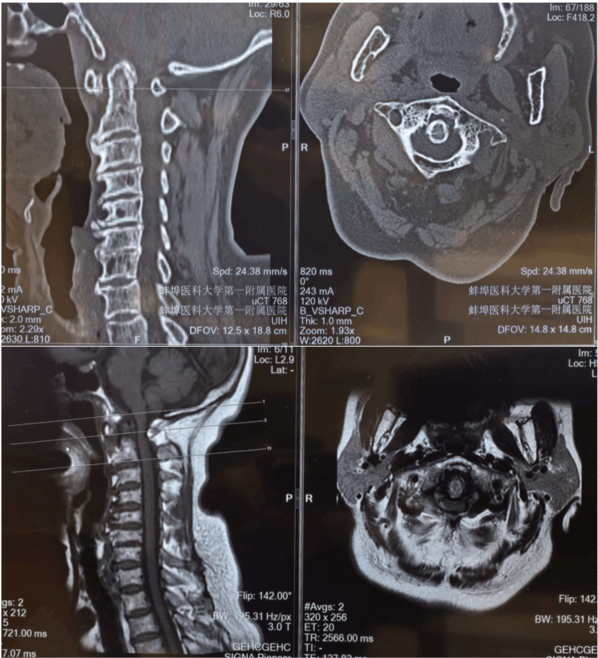

影像学检查显示,患者上颈椎椎管内韧带肥厚、骨质增生,已严重挤压脊髓,若不及时干预,可能导致四肢瘫痪、呼吸功能障碍等严重后果。传统开放手术需大范围剥离颈部肌肉,创伤大、出血多,且因上颈椎区域操作空间狭小,脊髓与神经血管密集,术中牵拉损伤、血管破裂风险极高。加之患者年事已高,合并高血压病史,传统手术的术后感染、恢复缓慢等问题让治疗陷入两难。